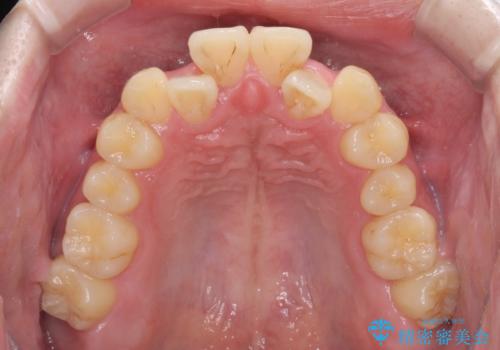

前歯のクロスバイト インビザラインによる矯正治療

- 上下のクロスバイトと前歯のデコボコを気にして来院された患者様です。

インビザラインを用い、IPR(歯と歯の間を削る)と歯列全体を拡大させることで、歯並びを整えていくこととしました。

上下ともに歯列全体を後方に移動させるため、上下の親知らずを抜歯することとしました。